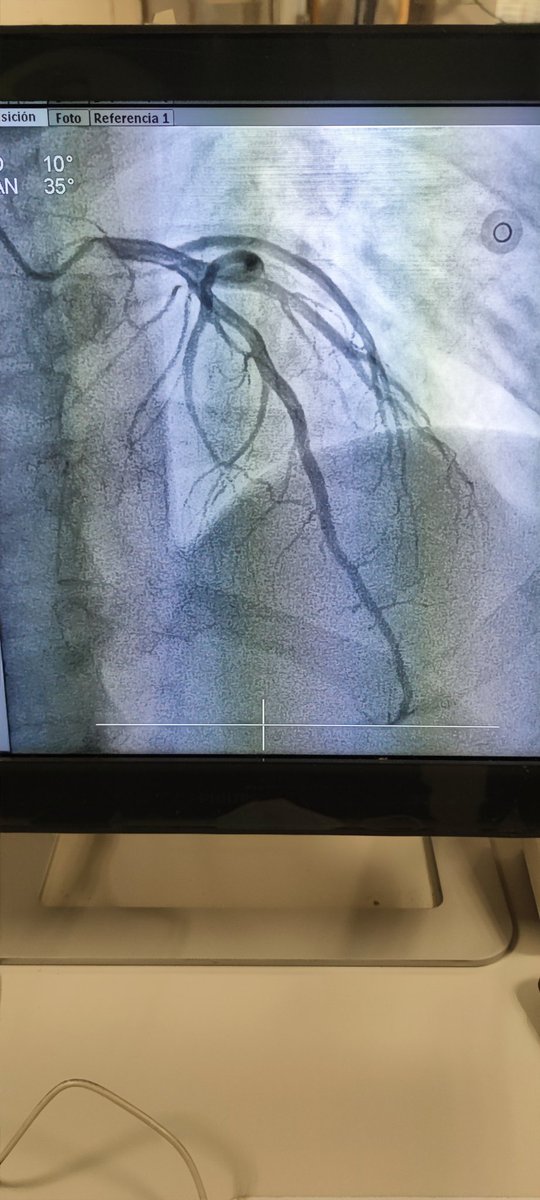

🫀⚡🧔🏻 45a, 🚬intenso, sedentario, obeso, HTA, #SICA #RadialFirst angio CD OTC agudizada TM disección ostial, Fullmetal CD 👌🏼 #MasterTheComplex #PCI #IVUS #Terumo #Azahi #BostonScientific #Medtronic